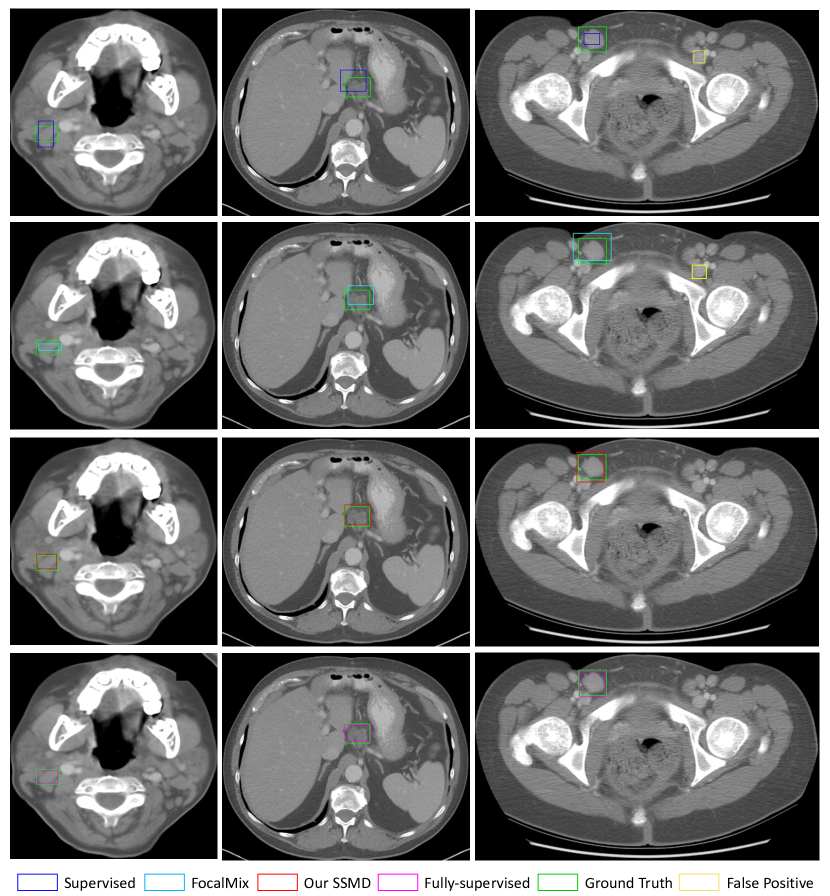

Refer to caption

Figure 7: Visual comparison of different methods in DeepLesion. The colors of these approaches are consistent with those in Fig.3. Additionally, we use yellow boxes to denote the false positive results.

5 Visualization

In Fig.6 and Fig.7, we visually compare the supervised model, FocalMix, our SSMD and the fully-supervised baseline to the ground truth in DSB 2018 and DeepLesion, respectively. These results again verify the effectiveness of proposed SSMD. As Fig.6 and Fig.7 display, SSMD is superior to FocalMix in two different aspects: precision and recall. In DSB, SSMD is able to predict more accurate bounding boxes for nucleus. In contrast, FocalMix sometimes misses small nucleus while SSMD has the ability to localize these hard cases and hence achieves higher recall. Moreover, SSMD is stronger on detecting severely overlapped nucleus, which demonstrates the strength of its learned powerful image representations. When we turn to DeepLesion, it is obvious that SSMD again produces more accurate box predictions. Besides, SSMD also shows its strength in reducing false positive predictions. When comparing SSMD with the fully-supervised baseline, we can see that SSMD achieves acceptable results in most cases. Besides the detection results, we also display the proposal results of the student and the teacher model in Fig.8. The results indicate that the teacher models produce better detection results than those of student models in both pairs of images. If we compare their predictions carefully, it can be seen that the predictions of the student model with consistency loss are more accurate and consistent (with predictions of the teacher model) than those without consistency loss. These phenomena verify the findings from [1] which shows the teacher model helps to improve the learning process of the student model.